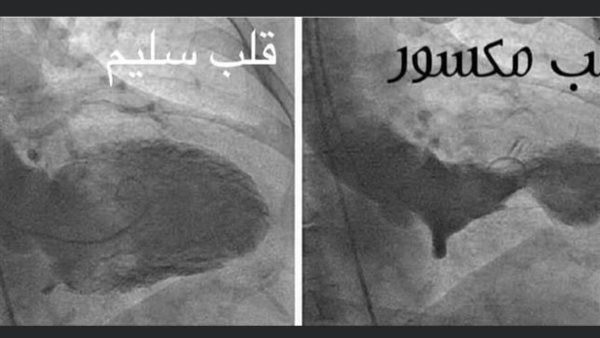

ونشر الدكتور جمال شعبان عبر حسابه بموقع فيسبوك، صورتين تجمع بين القلب السليم، والقلب المكسور -علامة على الحزن-، معلقًا: الزعل ممكن يعمل سكتة قلبية وموت مفاجئ كمان، بص للصورة اللي علي اليمين دا قلب مكسور، شوف الفرق بينه وبين الصورة اللي على الشمال قلب سليم، كسرة القلب والقلب المكسور نتيجة الزعل الشديد، حقيقة علمية ومتلازمة مرضية مش عبارة أدبية.

وأضاف الدكتور جمال شعبان: التفسير العلمي الزعل بينشط الجهاز العصبي السمبثاوي اللي بيفرز أدرينالين بكميات كبيرة جدًا، وبيسموها عاصفة الأدرينالين، والأدرينالين بيعمل اعتصار للقلب، وبيحصل انقباض في قاعدة القلب، وتمدد بالوني في قمة القلب، وزي ما هو باين في الصورة انكسار حقيقي للقلب، ورغم إن قسطرة الشرايين التاجية ممكن تطلع سليمة، علشان كدا في القرآن ربنا بيقًول لا تحزن، والرسول صلى الله عليه وسلم بيقًول لا تغضب.